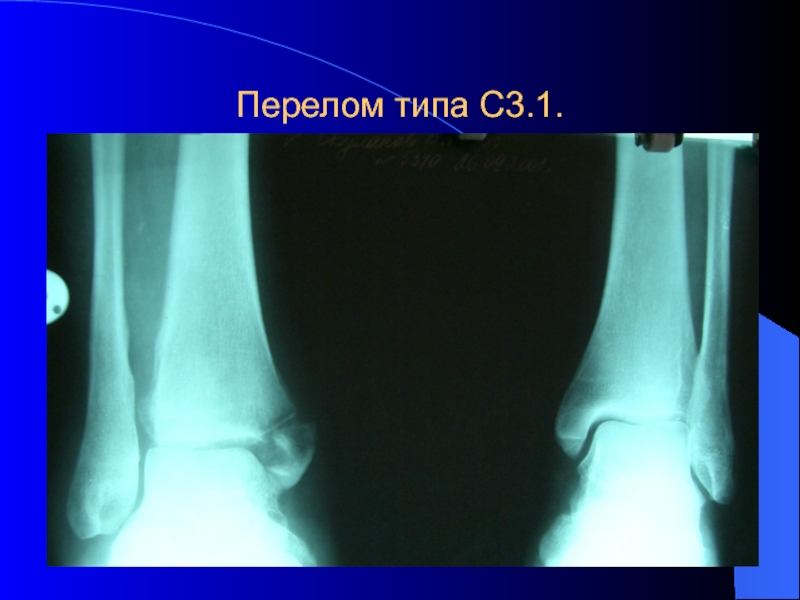

Слайд 18Перелом типа С3.1.

Перелом типа С3.1.